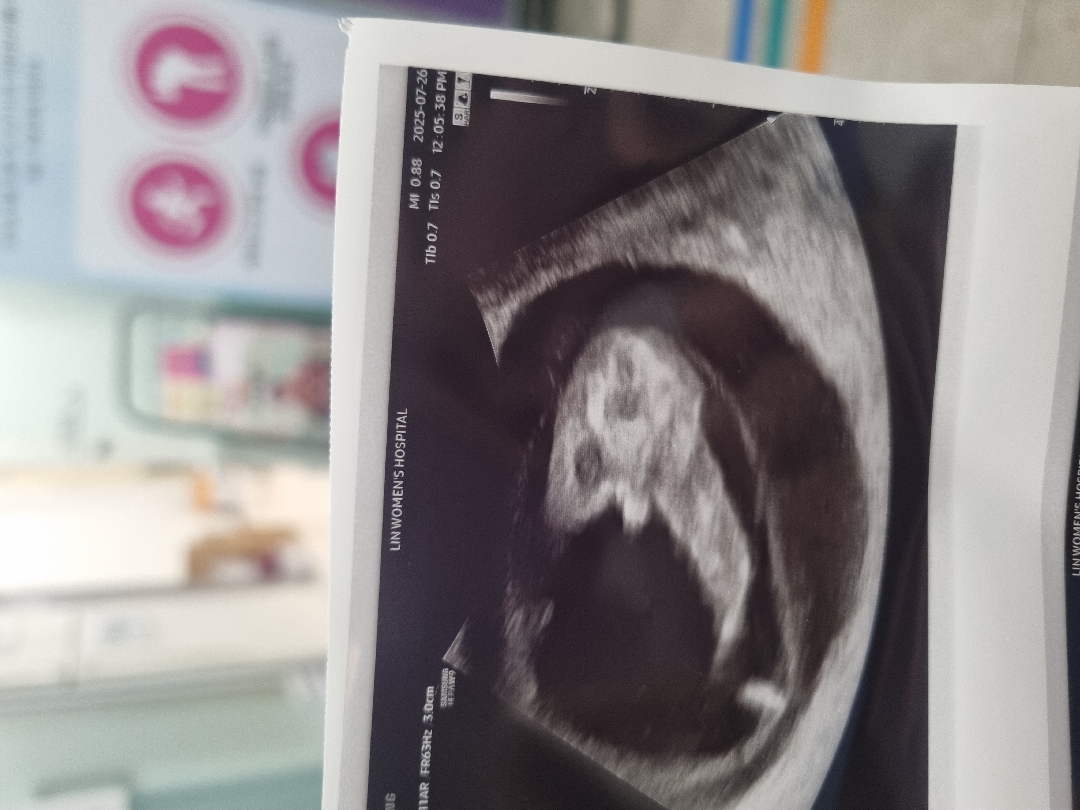

11주 1일인데 이건 빼박 아들일까요 ㅋㅋ 애기가 다리를 활짝 ㅎㅎ